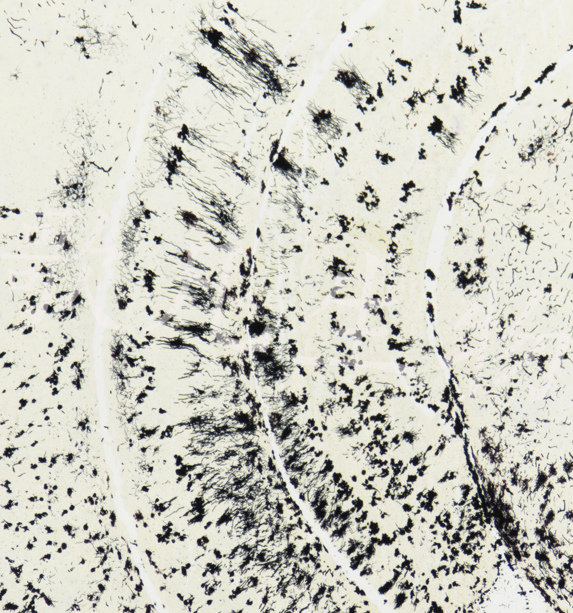

Golgi氏神经元神经纤维染色

Golgi-Cox浸染法是研究神经元和胶质细胞正常和非正常形态最有效的方法之一。使用Golgi技术,在药物处理过的动物脑中发现了神经树突和树突微小的形态改变。

神经元细胞、神经树突棘呈黑色,背景浅黄色